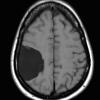

10A1 Cyst, arachnoid (Case 10) CT - Copy

10A2 Cyst, arachnoid (Case 10) FLAIR - Copy

10A3 Cyst, arachnoid (Case 10) T1noC - Copy

10A4 Cyst, arachnoid (Case 10) T2noC A - Copy